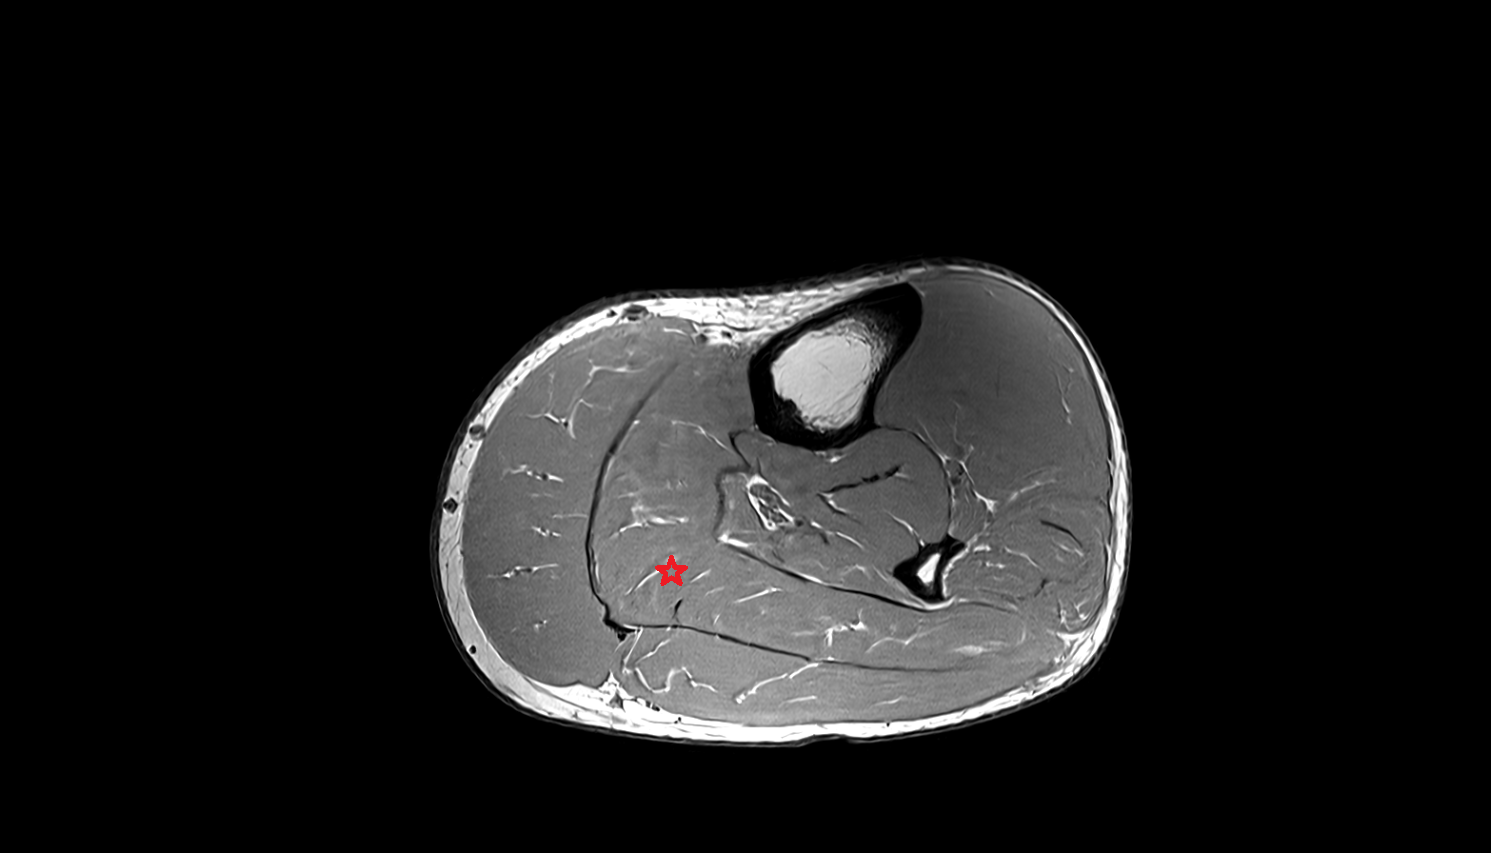

- Biceps femoris muscle (Short head)

- Biceps femoris muscle (Long head)

- Semitendinosus muscle

- Semimembranosus muscle

- Gastrocnemius muscle